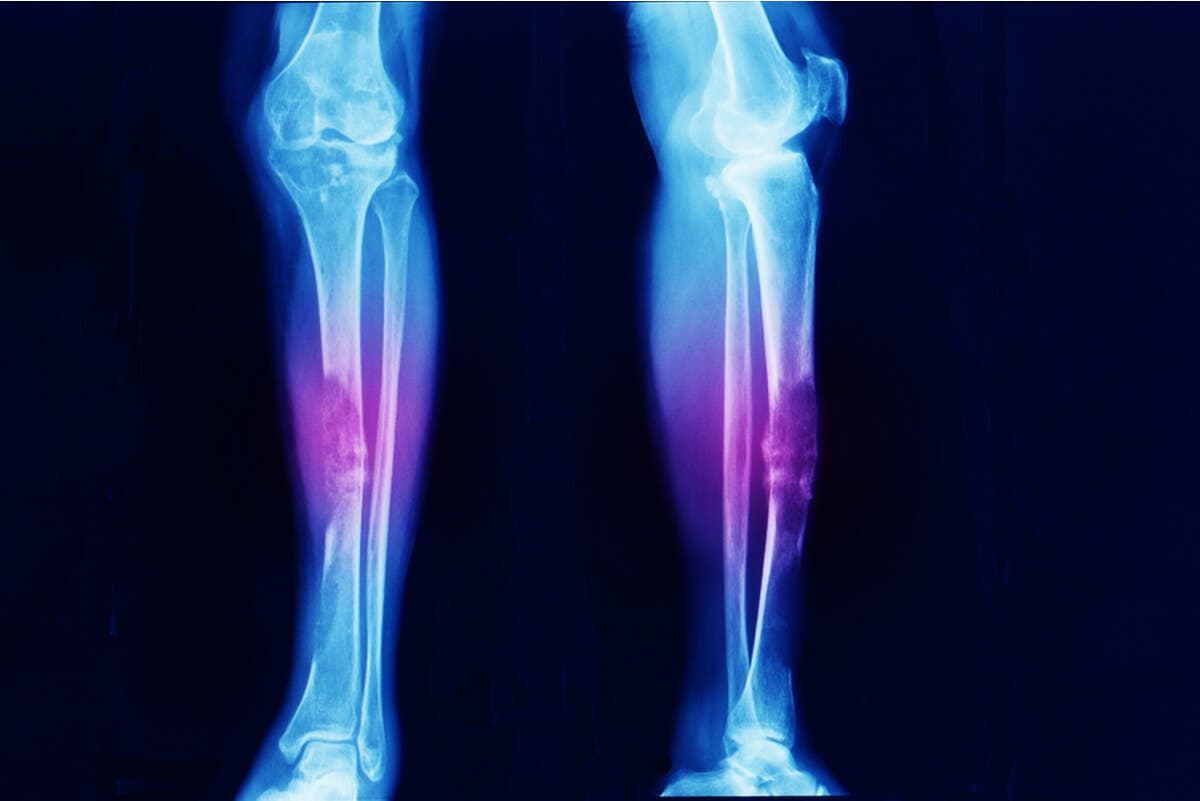

- Diagnosticar fracturas o traumatismos que no se observen en radiografías.